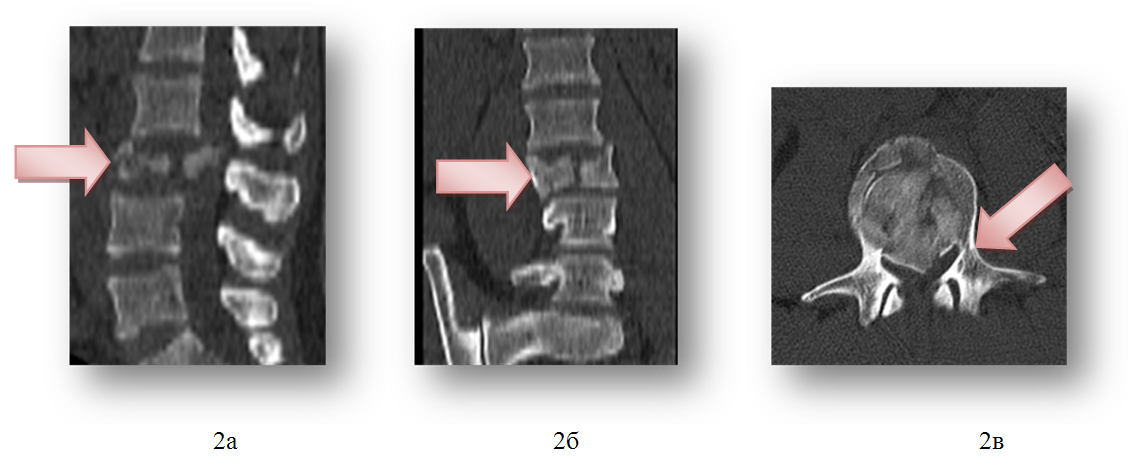

1) закрытый нестабильный, компрессионно-оскольчатый перелом тела и левого поперечного отростка 3 поясничного позвонка, перелом дуг 3-4 поясничных позвонков и субкомпенсированный стеноз позвоночного канала на уровне 3 поясничного позвонка, радикулопатия 4 поясничного корешка слева, посттравматическая кифотическая деформация позвоночника.